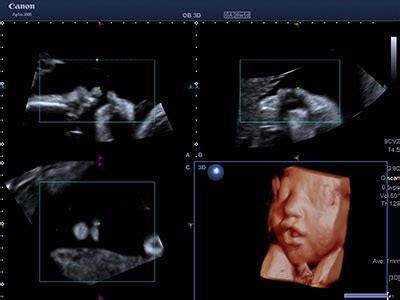

La flussimetria fetale rappresenta, ad oggi, la più importante metodica disponibile per riconoscere lo stato di salute intrauterino del feto. Ma in cosa consiste esattamente? L'esame utilizza una sonda addominale che emette onde sonore verso il feto; tali onde vengono riflesse e captate dall'ecografo, che le trasforma in immagini dinamiche. Il ginecologo, avvalendosi dell'Ecocolor Doppler e dell'Energy Color Doppler, è in grado di analizzare la direzione e la velocità del flusso sanguigno nei vasi sanguigni fetali e placentari.

Un momento cardine del percorso diagnostico è l'ecografia morfologica, che si esegue tra la 20ª e la 24ª settimana di gestazione. In questa occasione, il ginecologo effettua un controllo completo: misura il diametro della testa, controlla lo sviluppo degli organi (cuore, colonna vertebrale, braccia, gambe, fegato e reni), verifica la posizione della placenta e valuta la quantità di liquido amniotico. Parallelamente, la flussimetria materna, eseguita preferibilmente tra la 22ª e la 24ª settimana, permette di valutare lo stato di vascolarizzazione del lato materno della placenta, un indicatore cruciale per prevenire patologie come la gestosi. Successivamente, nel terzo trimestre, tra la 31ª e la 34ª settimana, viene solitamente effettuato un ulteriore esame per valutare la crescita fetale e il flusso sanguigno, garantendo che il bambino riceva un apporto ematico ottimale fino al momento della nascita.

Ecografia con flussimetria

Quando si parla di flussimetria fetale, non si può prescindere dalla qualità dell'attrezzatura ecografica e dall'esperienza dell'operatore. Il ricorso all'Ecocolor Doppler permette di visualizzare il flusso sanguigno con una precisione cromatica che aiuta il medico a identificare con chiarezza le resistenze vascolari. Un'elevata resistenza, rilevata precocemente, può essere il segnale d'allarme per l'avvio di un protocollo di monitoraggio più intensivo.